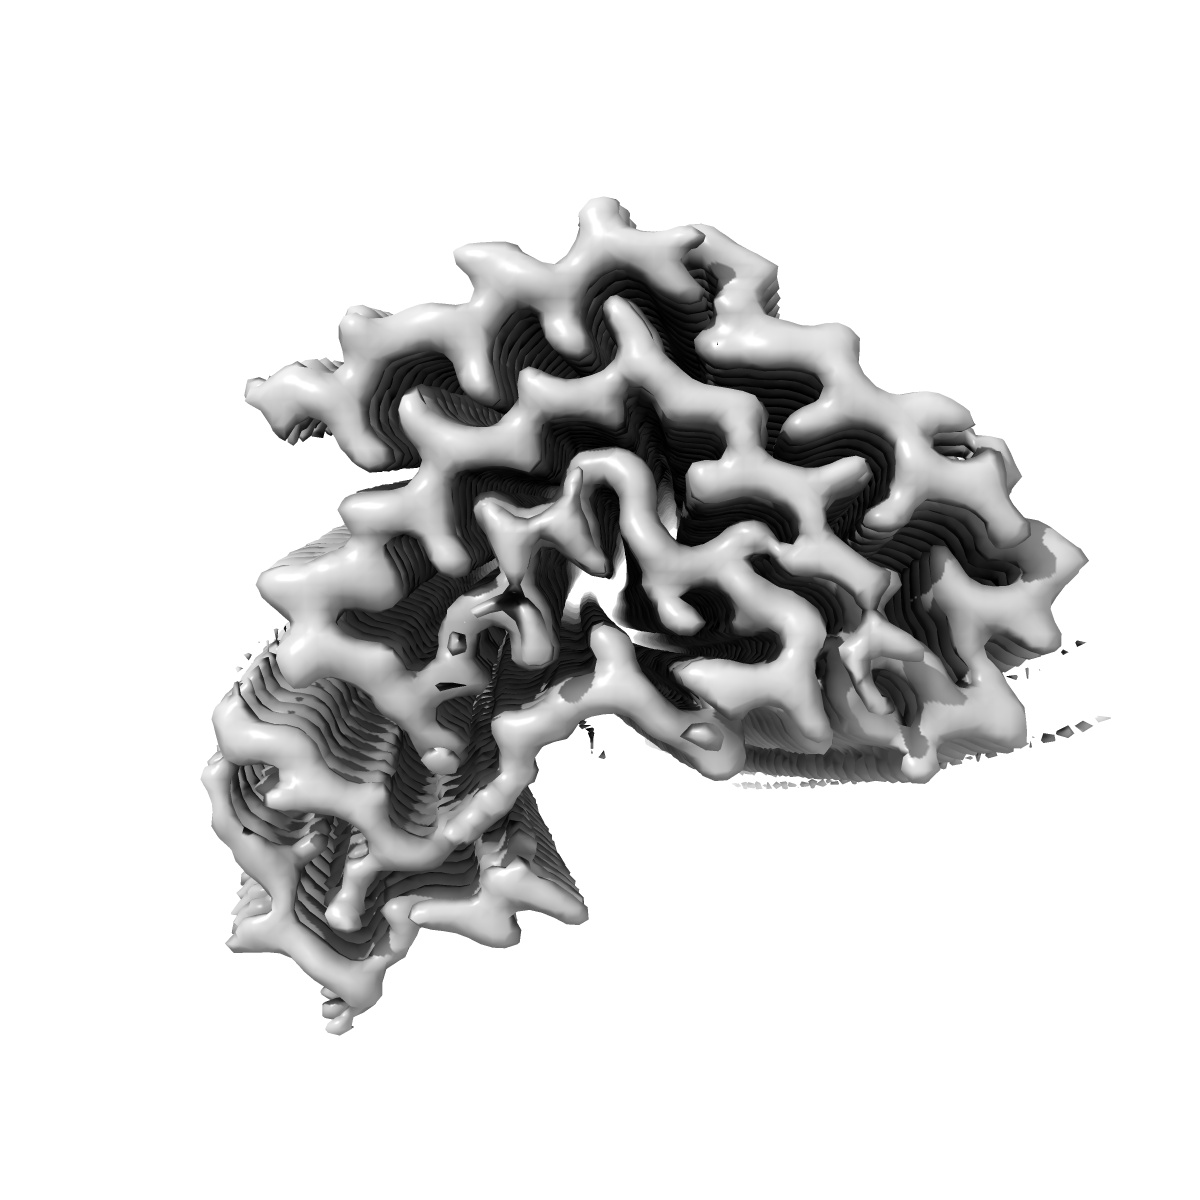

Structure of TDP-43 amyloid filaments from type A FTLD-TDP (individual 3, variant 1)

Sample: TDP-43 amyloid filaments extracted from the frontal cortex of an individual with type A FTLD-TDP

TDP-43 forms amyloid filaments with a distinct fold in type A FTLD-TDP.

Arseni D , Chen R, Murzin AG, Peak-Chew SY , Garringer HJ , Newell KL, Kametani F , Robinson AC , Vidal R , Ghetti B , Hasegawa M , Ryskeldi-Falcon B

(2023) Nature , 620 , 898 - 903